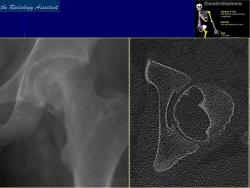

Хондробластома — это редкая доброкачественная опухоль, локализующаяся, главным образом, в эпифизе и отличающаяся своеобразным клеточным составом. Ткань новообразования представлена овальными, округлыми и веретеновидными клетками, напоминающими незрелые хондроциты (хондробласты). Зрелый гиалиновый хрящ определяется лишь в некоторых опухолях. Возраст больных варьирует. Мужчины поражаются в два раза чаше женщин. Пациенты предъявляют жалобы на боли в течение нескольких месяцев или лет, у некоторых больных определяются внутрисуставной выпот, припухлость и ограничение движений. Наиболее типичная локализация опухоли — проксимальные эпифизы плечевой и большеберцовой костей, а также дистальный эпифиз бедренной кости. У 20 % больных опухоль развивается в плоских или коротких трубчатых костях, преимущественно в пяточной и таранной. Изредка поражаются кости лицевого черепа, в том числе височная. В большинстве случаев новообразование выходит за пределы эпифиза и распространяется на метафиз. На фоне остеолиза обнаруживаются рассеянные участки обызвествления в виде пунктирных линий, а также разреженный трабекулярный рисунок. Хондробластома, как правило, не выходит за пределы кости, но изредка проникает в полость сустава. В процессе роста опухоли иногда возникает вторичная аневризматическая костная киста.

Рентгенологическая картина. Хондробластома выглядит как небольшой, от 3 до 6 см литический очаг, центрально или эксцентрично расположенный, с четкими контурами, занимающий около половины площади эпифизарной зоны. Хондробластома плоских костей и мелких трубчатых костей больших размеров, может сопровождаться припухлостью мягких тканей, вздутием кости и периостальной реакцией. Распространение процесса на метафизарную зону встречается часто.